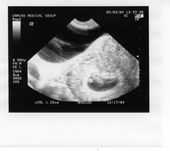

Tulia First Look

1.23cm Long

7 Weeks 3 Days (+/- 2Days) Old

This is our first look. Due to arrive on December 17, 2004. So they say....